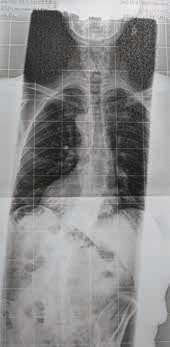

Von Kostenträgern und deren Gutachtern wird die Behandlung mit lediglich fixierenden Rahmenstützkorsetten oder Leibbinden aus Kostengründen favorisiert beziehungsweise als medizinisch ausreichend erachtet (Abb. 4a u. b). Keinesfalls können Fertigprodukte bei der Versorgung dieser Patienten eine zufriedenstellende Lösung sein. Wegen der noch dünnen Studienlage ist eine Argumentation in solchen Fällen mühsam und selbst über Sozialgerichtsurteile nicht immer zu erreichen.